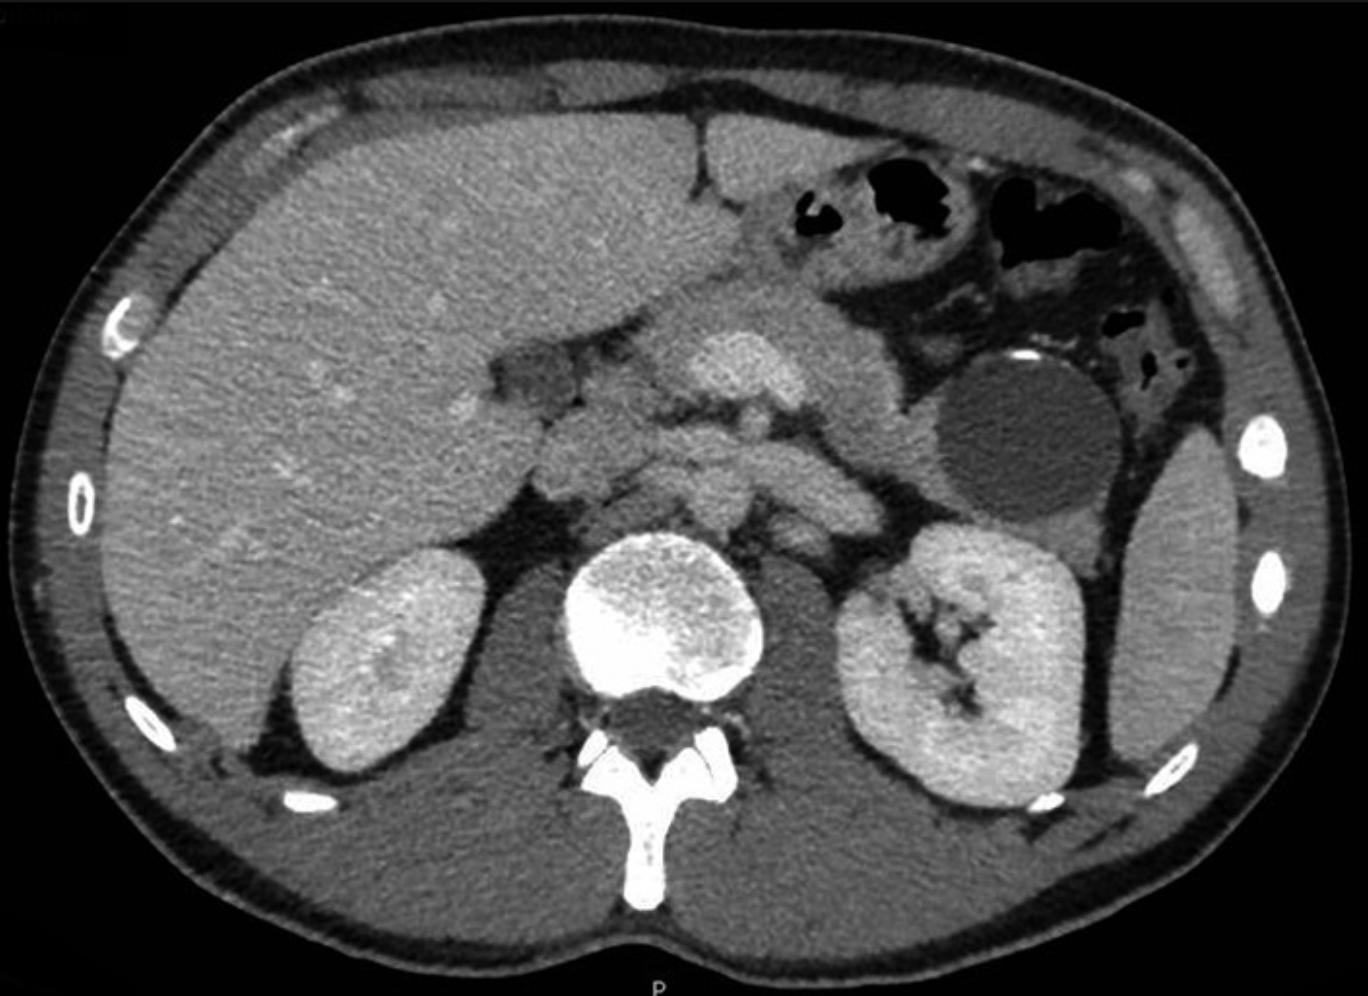

Material y métodos: Presentamos el caso de dicha patología en un varón joven que debutó con dolor en hipocondrio izquierdo y en la pruebas de imagen se evidenció una lesión quística en cola pancreática de 50x45mm, con calcificaciones lineales. Se realizó pancreatectomía distal.

Resultados: El diagnóstico anatomopatológico informó de transformación quística acinar.